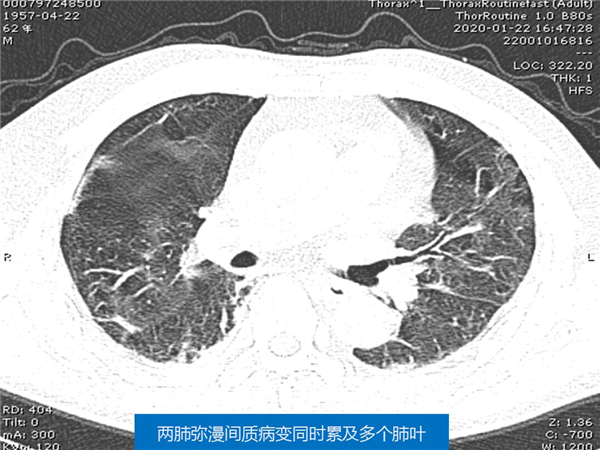

【病例分享】新型冠狀病毒感染肺部CT影像4例(常德市第一人民醫(yī)院)

幻燈片5.jpg